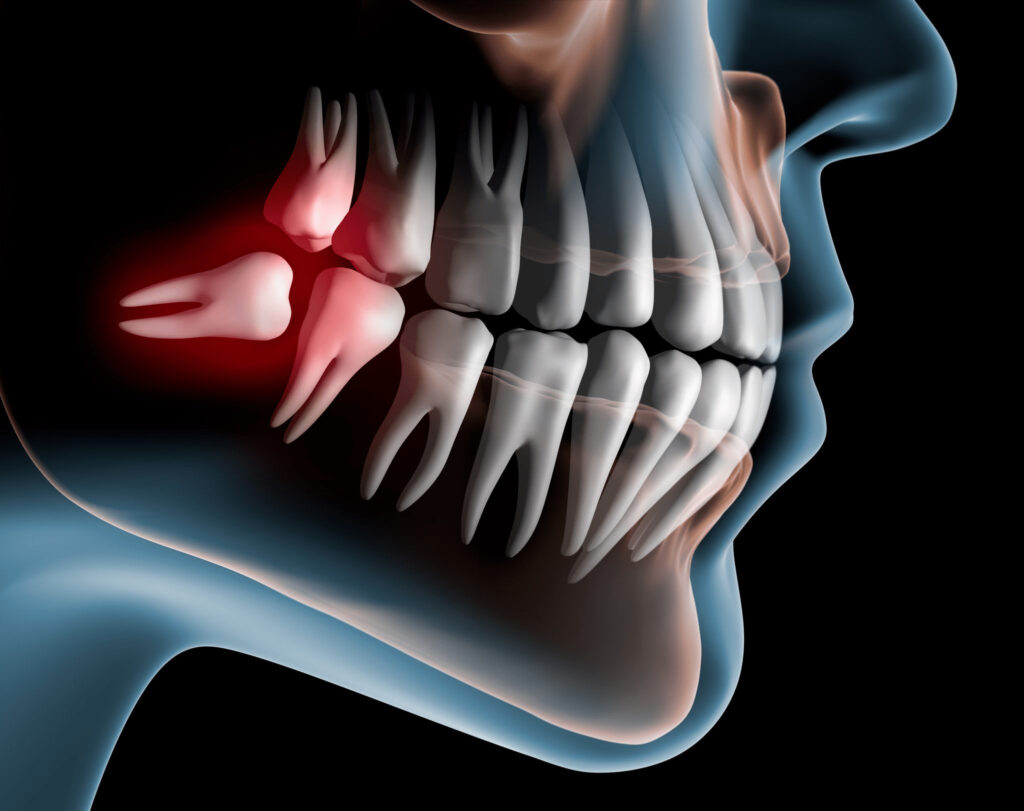

親知らずが横や斜めに生えてきたり、歯ぐきがかぶっていることがあります。そのため、親知らずの周囲には細菌が残りやすく、以下のようなトラブルを起こし、痛みの原因になります。

- 親知らずの周りの歯ぐきが腫れる(智歯周囲炎)

- 親知らずが咬み合わせに影響を与え、顎関節症になる

親知らずが周囲に悪影響をもたらしている場合は、早めの抜歯をお勧めしています。

- 第2大臼歯の歯の根に、親知らずが当たっている